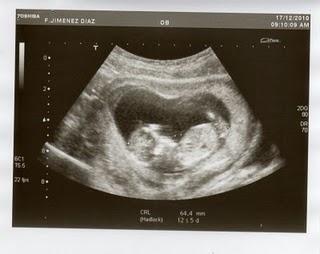

El día 17 de diciembre de 2010, en torno a las 8:30 de la mañana, M. y yo entrábamos en un hospital de Madrid para que le hicieran una ecografía. A esa misma hora, mi familia entraba con mi madre en un hospital de Zamora para que comprobaran su estado de salud, muy endeble en los días previos. Un niño gestado tres meses atrás estaba en camino: la eco mostró que estaba sano, que estaba bien, que había vida. No se lo habíamos contado a nadie por consejo del médico. Salimos eufóricos del hospital. Yo imaginaba la reunión familiar que tendríamos el 23 de diciembre para anunciarlo entre risas y champán. Apenas tres o cuatro horas después mi hermana me llamó para decirme que nuestra madre tenía metástasis en el hígado. Los médicos dijeron que no pasaría del fin de semana. Y así fue, como ya sabéis muchos de vosotros: falleció el 19, por la mañana. El 17 de diciembre me dieron una de las mejores noticias de mi vida y también una de las peores noticias de mi vida. Así que M. y yo nos hemos debatido durante estos días entre el dolor y la alegría, entre la risa y el llanto, entre la pena y el júbilo, con ese secreto que nos carcomía por dentro y que nunca pudimos contar a mi madre porque ya era demasiado tarde. Hasta ayer no se lo hemos dicho a la familia. Durante este año, pero sobre todo en las dos últimas semanas, M. y yo hemos zozobrado entre lo que se va y lo que viene, entre lo que va a morir y lo que va a nacer, entre lo que empieza a latir y lo que está dejando de palpitar, entre la gestación y la agonía, entre la salud y la enfermedad. Tal vez a algunos os parezca frío o extraño o impúdico que lo cuente aquí, que lo anuncie en un blog. Sin embargo, en los últimos días he aprendido a mover ficha antes de que sea demasiado tarde. Llevaba meses dándole vueltas a la escritura de una novela relacionada con estos temas (vida y muerte, nacimiento y enfermedad, memoria y olvido) y ahora, por suerte y por desgracia, ya conozco el final de ese libro. Aunque empezaré a escribirlo en febrero o marzo, prefiero que sepáis el argumento. Por si acaso me muero antes de poder acabarlo; nunca se sabe. Para que no quede en el olvido. Esto no es un cuento, aunque parezca una película, una tragicomedia en montaje paralelo. No, amigos, esto es la puta realidad, que no deja de envolverme en su desbarajuste de sorpresas. Feliz navidad.